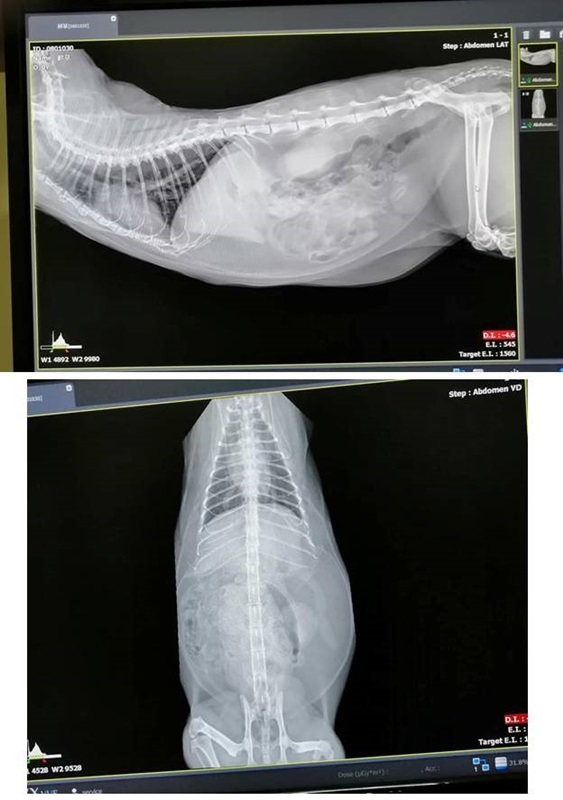

鮮草目前仍需持續回診追蹤檢查、調整用藥,在12月27日至沐恩醫院回診時,發現血糖指數升高, 開始服用降血糖藥物,1月3日再度回診,血糖指數又升高太多而住院治療、進行血糖監測,至1月11日較為穩定後接回照護,現在必須於早晚醫師指定的時間給定量食物及打胰島素針劑,每周回診追蹤血糖變化。

至今血糖指數已逐漸下降,但還未完全到標準值,須再持續一段時間的打針,本筆醫助為鮮草自1月3日至1月22日於沐恩的醫療費用,包含住院、檢驗、針劑用藥,希望大家能夠一起幫忙乖巧的鮮草,謝謝大家。

鮮草因血糖過高、有糖尿病而住院,現在情況較為穩定可出院照護,須每天早晚打胰島素針,醫師說明,造成鮮草糖尿病的原因,可能是長期服用類固醇或是變胖太多,還無法確定胰島素須要打多久,如果鮮草的糖尿病是可復原的,會隨著時間調整劑量,要回診監控,且即使在治療打針中也還是可能有很小的機率出現低血糖情況。

血檢結果,血糖指數45(住院時429,正常值是74-159),膽固醇及三酸甘油脂的指數正常,表示這三天內血糖控制得不錯。

醫師說明,指數45偏低,但依據早晚打胰島素的時間,下午2點原本就是一天內血糖的最低點,現場有先給鮮草吃一些罐罐。

因血糖指數已下降,可開始逐漸減少胰島素劑量及增加下午一餐,下次回診再有進步,可以停皮下輸液。